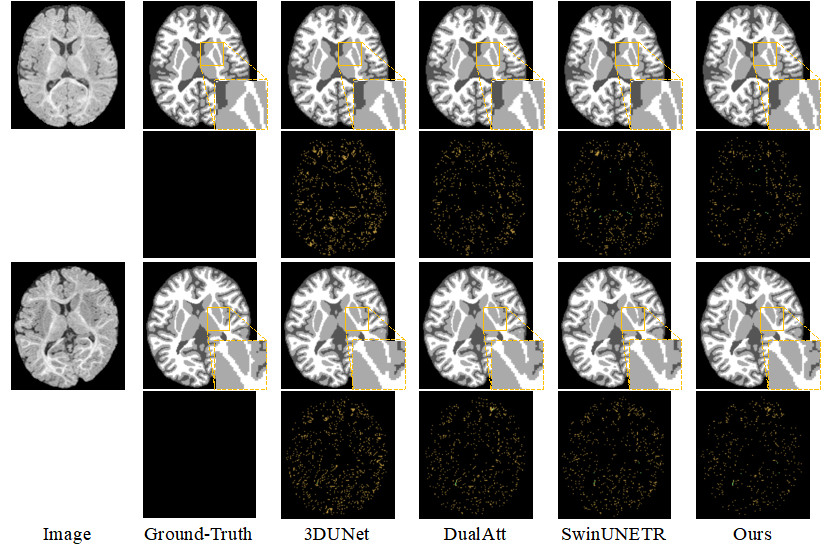

◆Adult-like Phase and Multi-scale Assistance for Isointense Infant Brain Tissue Segmentation, MICCAI 2023, Vancouver, Canada, October 8-12, 2023. [Jiameng Liu, Feihong Liu, Kaicong Sun, Mianxin Liu, Yuhang Sun, Yuyan Ge, Dinggang Shen]

精确且自动的脑组织分割对于婴儿发育跟踪和早期脑部疾病诊断至关重要。然而,由于新生儿出生后的第一年中存在的髓鞘化和成熟过程,大约在6个月左右 (等密度阶段),MRI 数据中灰质和白质之间的强度对比极低。这使得对等密度阶段脑组织的自动分割变得困难,即使是手动标注也是如此。针对这一问题,我们提出了一种利用成人相似期数据 (12个月左右) 的结构先验和更大感受野的脑组织来辅助等密度阶段数据的脑组织分割的方法。具体而言,我们利用大量已经标注的成人相似期脑组织数据生成等密度阶段的脑组织数据,以解决等密度阶段标注数据少的问题。同时,将生成的等密度期数据与成人相似期数据进行配对,作为结构先验,以增强等密度期模糊的组织边界。我们的实验结果表明,相较于现有方法,我们提出的方法在定量和定性方面都取得了显著的改进。这一方法有助于更加准确地测量脑发育并实现更早期的脑部疾病诊断。